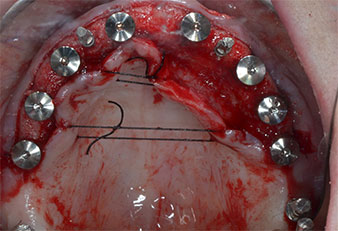

Uno strumento piezoelettrico (Piezomed I1) a forma di fiamma, rivestito in diamante, è stato usato per contrassegnare le posizioni dell'impianto e per eseguire una preparazione pilota (Fig. 3). Si è prestato attenzione a utilizzare un movimento verticale ascendente e discendente, con potenza ridotta, irrigazione completa e bassa pressione (inferiore a 300 g). Successivamente è stato applicato uno strumento pilota (Piezomed I2A/I2P) per l'ingrandimento iniziale delle sedi dell'impianto del diametro di 2 mm (Fig. 4), seguito da un inserto da 3 mm (Fig. 5).

A causa dell'osso relativamente duro (D2) in quest'area, le sedi dell'impianto di 10 mm nelle posizioni 11 e 21 sono state finalizzate con un trapano rotante da 4 mm di diametro, in combinazione con un contrangolo chirurgico W&H WS-75 L, il motore per impianto W&H Implantmed e il modulo opzionale Osstell ISQ di W&H. Al contrario, a causa dell'osso morbido, le sedi posteriori sono state preparate a un diametro finale di 3 mm utilizzando lo strumento Piezomed I3P. Gli impianti sono stati infine posti per via transgengivale sull'osteointegrato per tre mesi (Figg. 6-10). La protesi dentaria esistente è stata mantenuta su quattro impianti provvisori (Fig. 8).